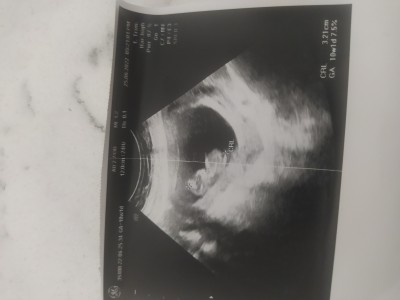

Kizlar 10haftalik hamileyim acaba cinsiyetini tahmin edenler varmi bi tane oglum var  cok merak ediyorumm saglicakla gelsin bebegim

Gebelik haftası 10